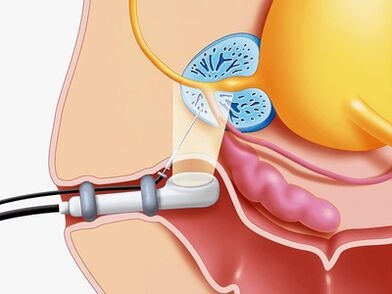

- Un complexe de méthodes instrumentales (échographie).

Examen échographique

Si une maladie de la prostate est suspectée, un examen échographique de la glande elle-même (échographie transrectale), les reins et la vessie sont optimaux, ce qui signifie que nous pouvons déterminer:

- Volume et taille de la glande.

- Présence de pierres.

- Tailles des bulles de graines.

- Condition des murs de la vessie.

- Urine résiduelle.

- Structures du scrotum.

- Un autre type de pathologie.